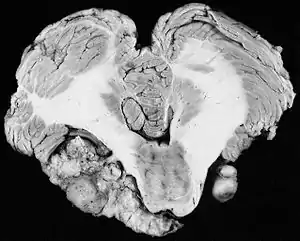

| Bilateral schwannomas in a patient with neurofibromatosis 2 | |